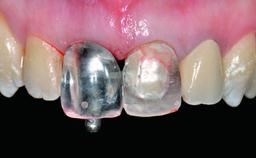

Replacement of a Compromised Upper Right Central Incisor: Hard- and Soft-tissue Augmentation, Late Placement of an RC Bone Level Implant

A 36-year-old male patient with a compromised maxillary central incisor was referred by his general dentist for consultation. The patient’s chief complaints were the gradual debonding of a temporary crown on the right central incisor and unsatisfactory esthetics due to an increasing diastema between the right central and lateral incisors. The patient reported a traumatic event some years previously, when a crown had been placed after root-canal treatment. The referring dentist wanted to provide a new crown restoration, but was concerned about the condition of the residual root. Anamnesis was negative for any other dental or periodontal pathology in the remaining dentition. The patient reported taking no medications: He was a smoker (10 to 15 cigs/day) and had realistic esthetic expectations.

Prosthesis Type FDP

Abutment Type CAD/CAM